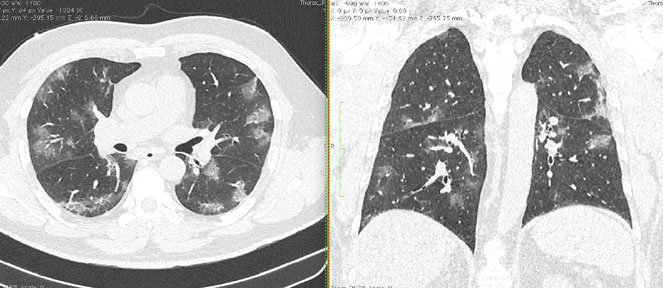

4.3. ЛУЧЕВАЯ ДИАГНОСТИКА COVID-19

Методы лучевой диагностики применяют для выявления COVID-19 пневмоний, их осложнений, дифференциальной диагностики с другими заболеваниями легких, а также для определения степени выраженности и динамики изменений, оценки эффективности проводимой терапии.

К методам лучевой диагностики патологии ОГК пациентов с предполагаемой/установленной COVID-19 пневмонией относят:

- Компьютерную томографию легких (КТ),

Стандартная РГ имеет низкую чувствительность в выявлении начальных изменений в первые дни заболевания и не может применяться для ранней диагностики. Информативность РГ повышается с увеличением длительности течения пневмонии. Рентгенография с использованием передвижных (палатных) аппаратов является основным методом лучевой диагностики патологии ОГК в отделениях реанимации и интенсивной терапии (ОРИТ). Применение передвижного (палатного) аппарата оправдано и для проведения обычных РГ исследований в рентгеновском кабинете. В стационарных условиях относительным преимуществом РГ в сравнении с КТ являются большая пропускная способность. Метод позволяет уверенно выявлять тяжелые формы пневмоний и отек легких различной природы, которые требуют госпитализации, в том числе направления в ОРИТ.

КТ имеет высокую чувствительность в выявлении изменений в легких, характерных для COVID-19. Применение КТ целесообразно для первичной оценки состояния ОГК у пациентов с тяжелыми прогрессирующими формами заболевания, а также для дифференциальной диагностики выявленных изменений и оценки динамики процесса. КТ позволяет выявить характерные изменения в легких у пациентов с COVID-19 еще до появления положительных лабораторных тестов на инфекцию с помощью МАНК. В то же время, КТ выявляет изменения легких у значительного числа пациентов с бессимптомной и легкой формами заболевания, которым не требуется госпитализация. Результаты КТ в этих случаях не влияют на тактику лечения и прогноз заболевания при наличии лабораторного подтверждения COVID-19. Поэтому массовое применение КТ для скрининга асимптомных и легких форм болезни не рекомендуется.

Вместе с тем, комплексная оценка анамнестических, клинических и рентгенологических данных позволяет определить клинически подтвержденный случай COVID-19, маршрутизировать пациента и начать противовирусную терапию.